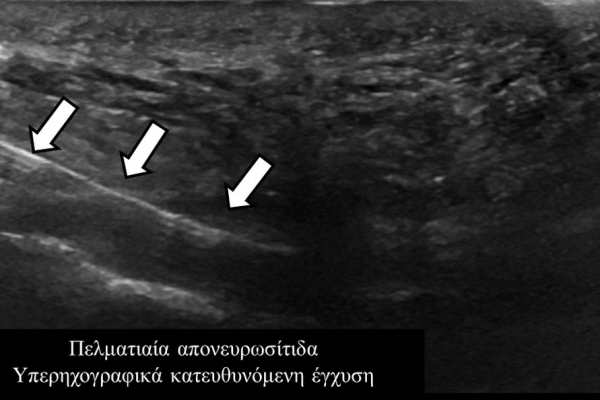

Οι διαγνωστικές-θεραπευτικές εγχύσεις είναι δυνατόν να γίνουν σε μια πλειάδα μυοσκελετικών-ρευματολογικών παθήσεων όπως:

- σε πελματιαία απονευρωσίτιδα